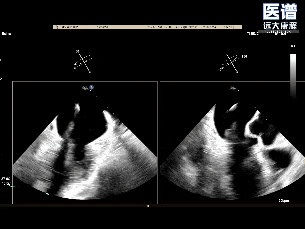

TEE-3D

TEE-3D血流

释放后3D评估(组织桥稳定)

释放后3D评估(反流少量)